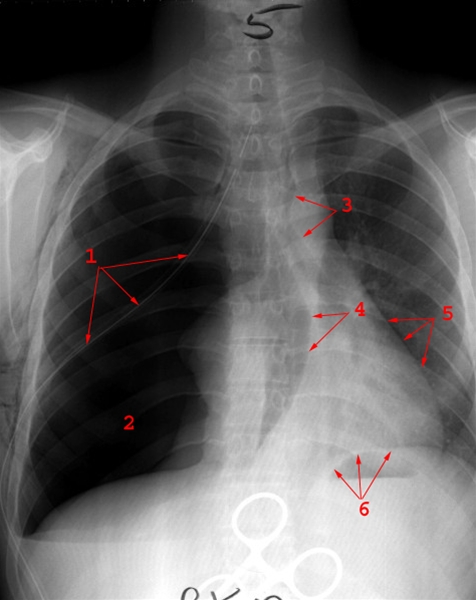

Billedet viser højresidig pneumothorax. Ventileffekt med betydelig overskydning af mediastinum (trykpneumothorax) mod raske side (venstre).

1. Dræn

2. Luftfyldt lungehule

3. Luftveje (pilene står over og under luftrørs deling til hovedbronkierne (carina))

4. Højresidig hjerteskygge

5. Venstresidig hjerteskygge

6. mellemgulvet (Diafragma)